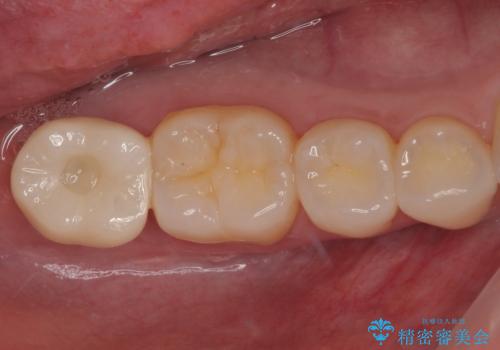

抜歯された骨の穴は、インプラント埋入時にはまだ大きな窩洞となっていましたが、径の大きいワイドインプラントを選択することで、埋入時に十分な安定を獲得することができました。

後方には欠損が残っていたため、補填材を填入しました。

術後にインプラントが骨から脱落することがありますが、特筆するトラブルなどなく、最短の3ヶ月で治療を終えることができました。